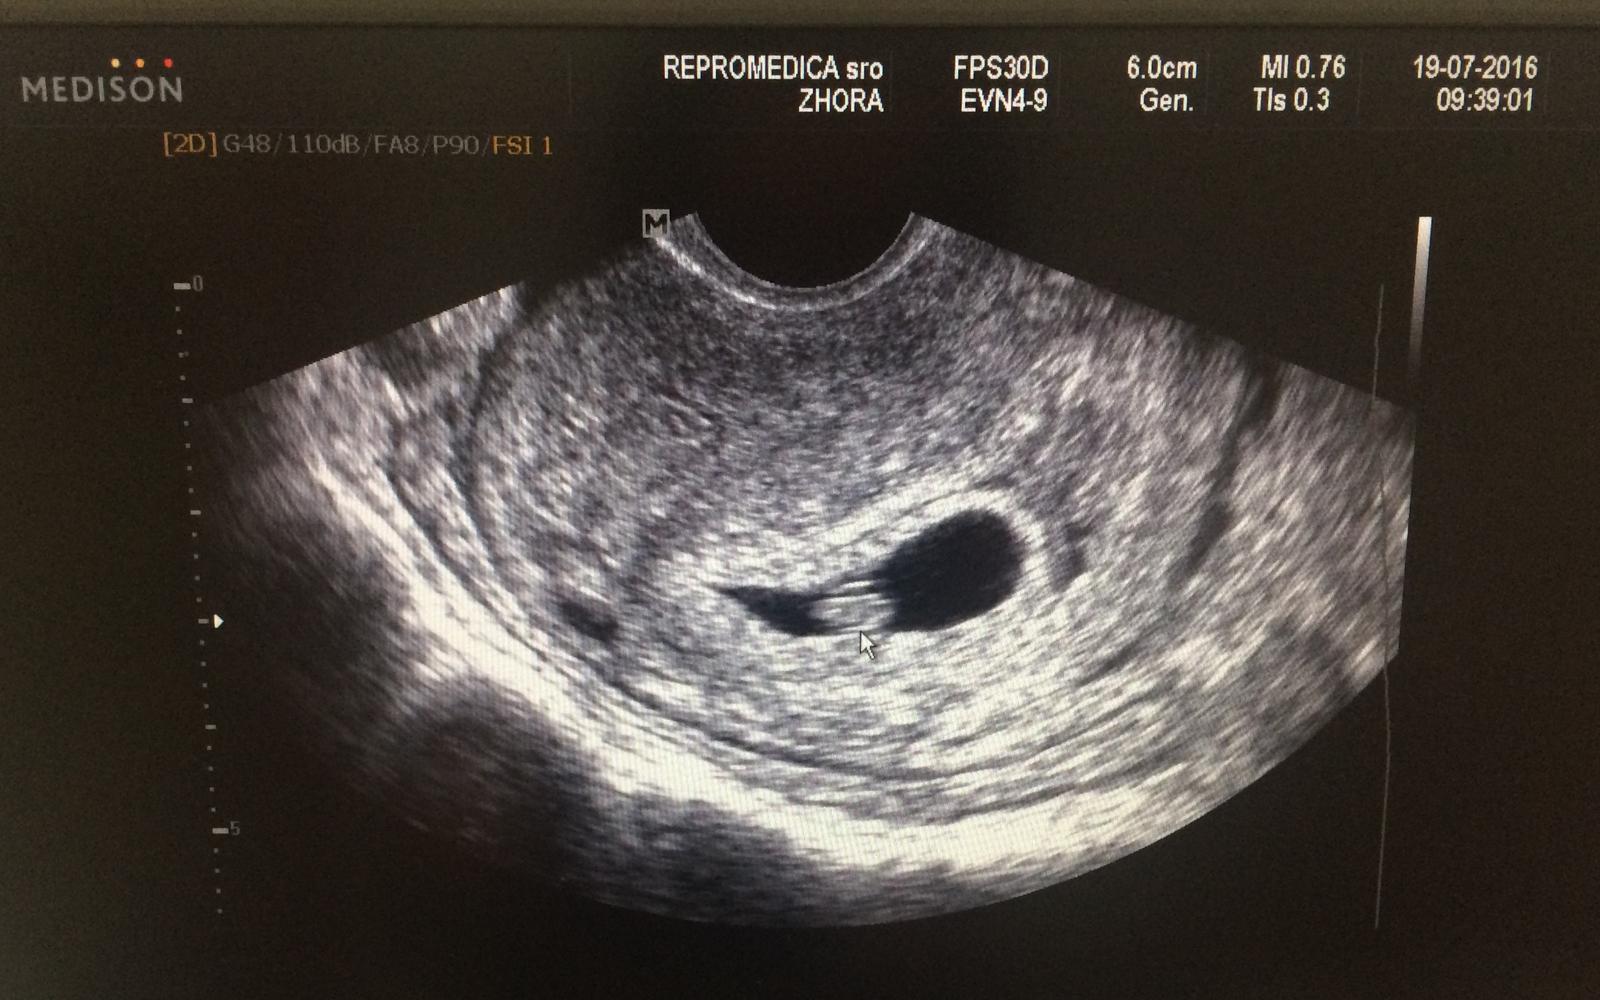

Dnes som bola v Repromedice na 1sono a dr.Drábek potvrdil srdiečko aj velkost na 6tt+3 9mm. Ej, veľmi milý doktor😍 A sestra moja ide dnes na 1.konzultaciu😉

@isabellita supeeeer, krasny obrazok 🙂